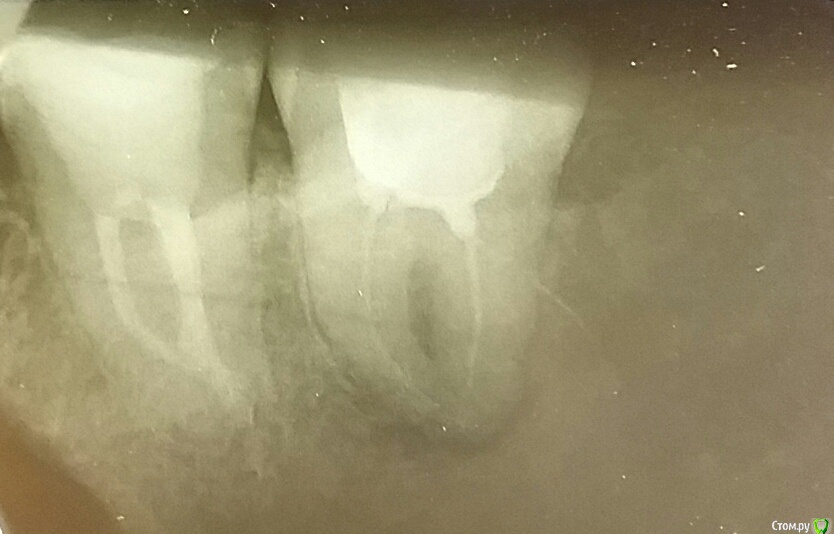

арбузова Опубликовано 7 июня, 2017 Автор Поделиться Опубликовано 7 июня, 2017 (изменено) Вот зуб) Изменено 7 июня, 2017 пользователем арбузова Ссылка на комментарий

red_butler Опубликовано 8 июня, 2017 Поделиться Опубликовано 8 июня, 2017 Вот зуб)Я бы этот зуб удалил Ссылка на комментарий

red_butler Опубликовано 9 июня, 2017 Поделиться Опубликовано 9 июня, 2017 почему?требуется повторное лечение корневых каналов с последующим протезированием Ссылка на комментарий

арбузова Опубликовано 9 июня, 2017 Автор Поделиться Опубликовано 9 июня, 2017 Так плохо полечили? При увеличении, вроде, в каналах какое-то наполнение видно. Ссылка на комментарий

St. Опубликовано 6 июля, 2017 Поделиться Опубликовано 6 июля, 2017 Не подскажете, я так и не поняла, что у меня с зубом? Каналы не все запломбировали? Киста? Или чего ещё? За пределами корня зуба воспаление( то что вы назвали "киста"), потому что каналы заполнены материалом не очень плотно и "продезинфицированы" недостаточно. Все дело усложняется тем что зуб находится далеко, да и впринципе 8 зубы чаще всего имеют сложное строение каналов и в условиях муниципальной поликлиники адекватно их полечить мягко говоря непросто. Поэтому если оставить как есть , то в любой момент как только иммунитет ослабнет зуб разболится, еще и щека припухнуть может. Поэтому Я бы этот зуб удалил А перелечивать как положено это сложно, дорого и долго. И в случае 8 зубов чаще всего не имеет смысла из рациональных соображений. 2 Ссылка на комментарий